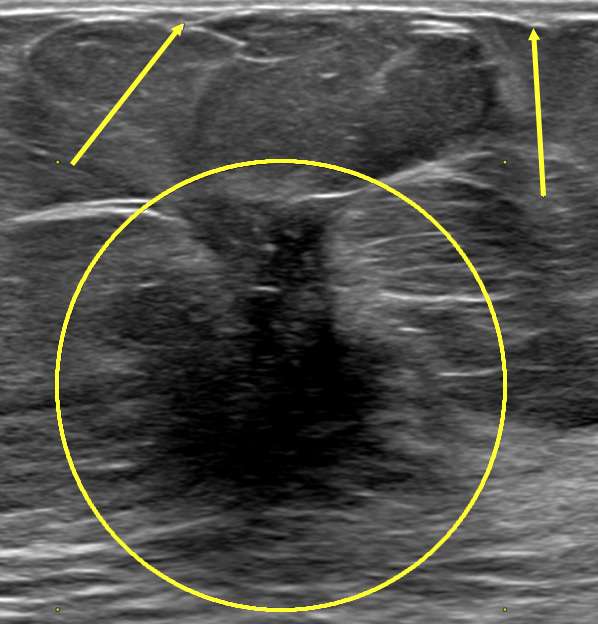

- Ultrasound: May further reveal distortion in the skin layers but is most helpful in further evaluating the presence of an underlying mass causing the retraction.

- Ultrasound: The nipple/subareolar area is difficult to evaluate on ultrasound because of the dark shadowing typically seen in this area. However, despite the difficulty of visualizing this area, sometimes masses may be seen. Additionally, ultrasound is helpful in evaluating for potential lymph node involvement in the setting of malignancy.